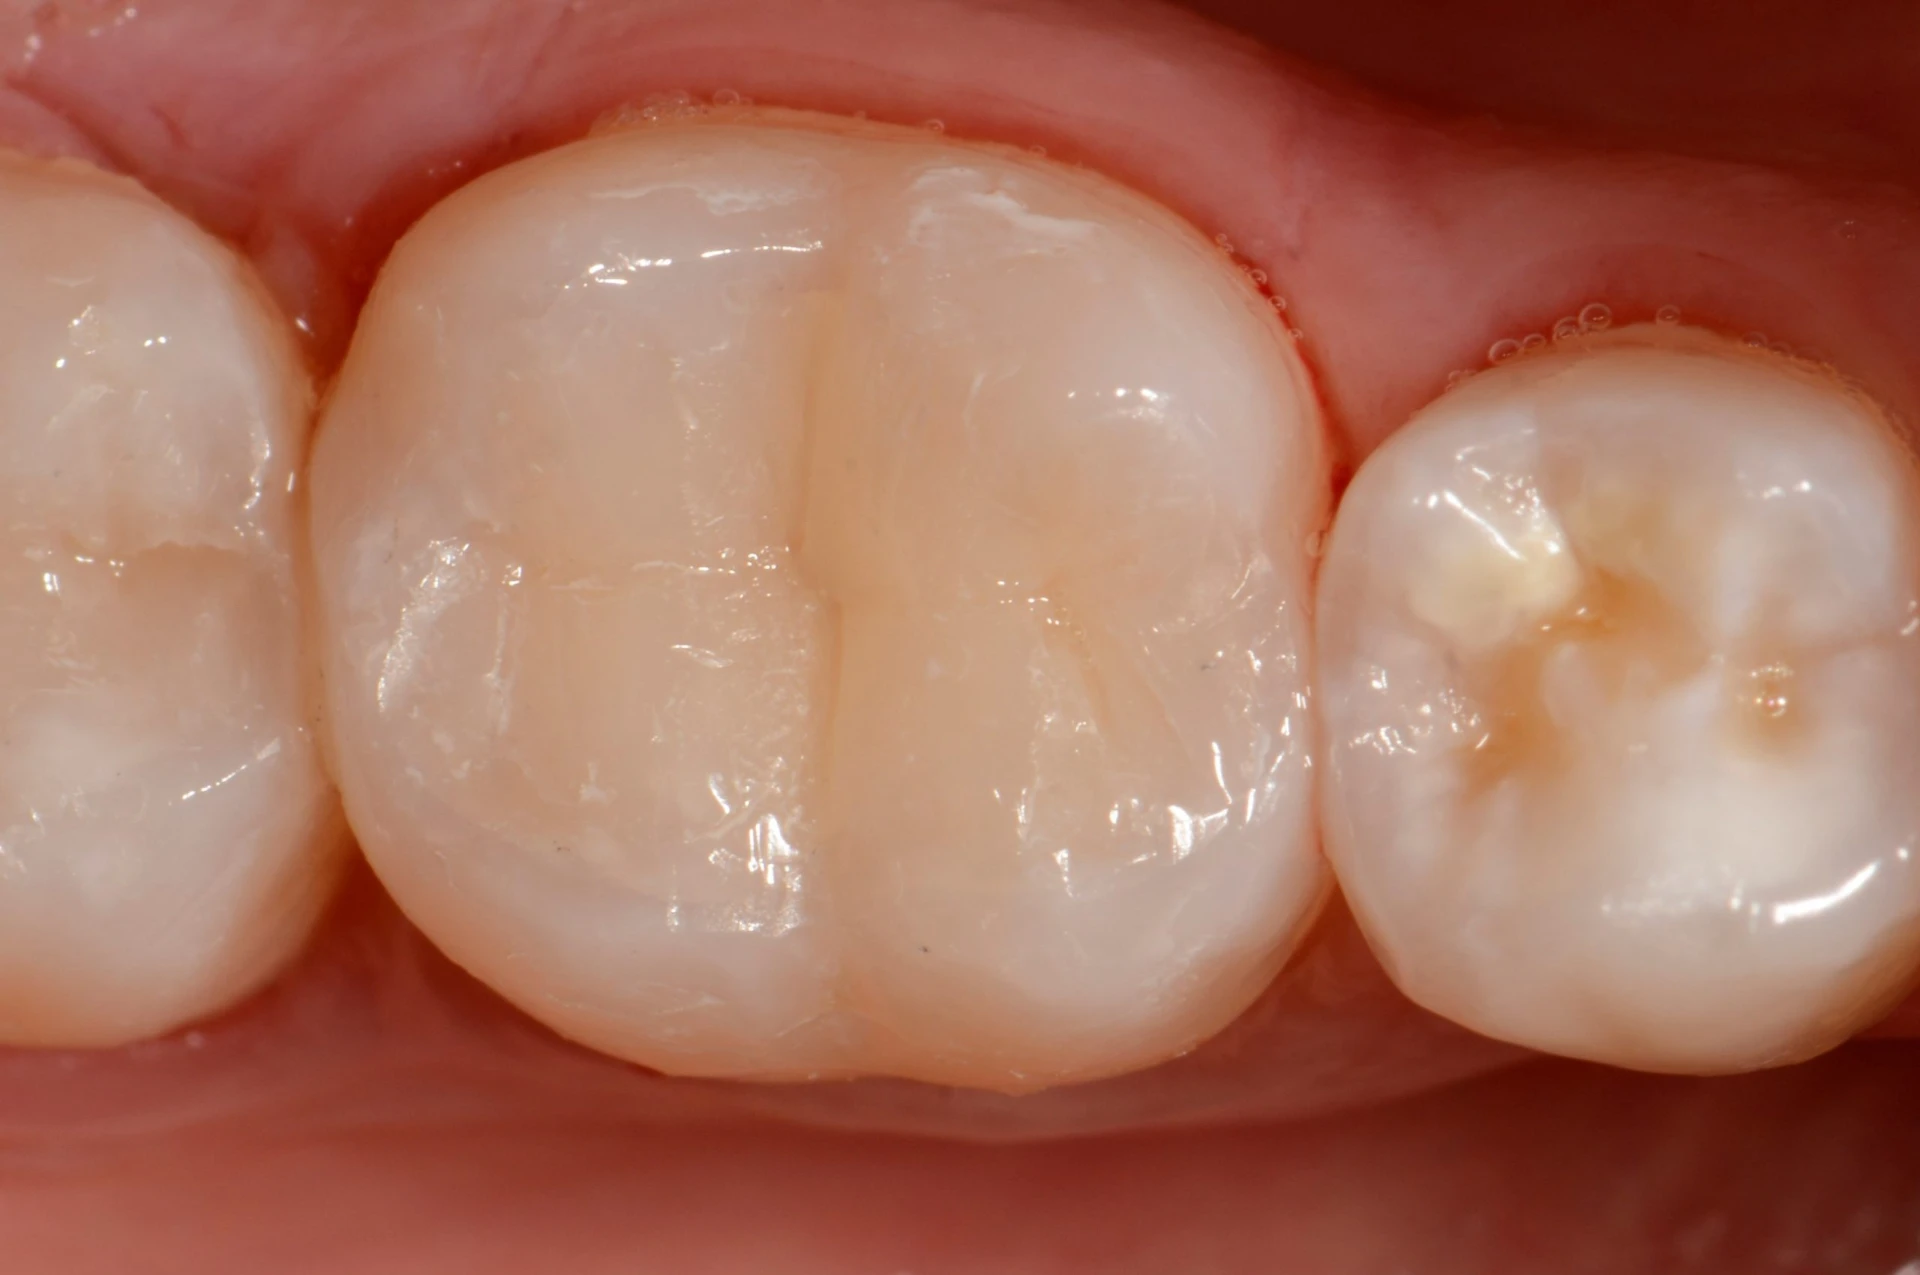

Confira este caso clínico de restauração dentária posterior, terceiro molar, com a resina tipo Bulk da 3M.